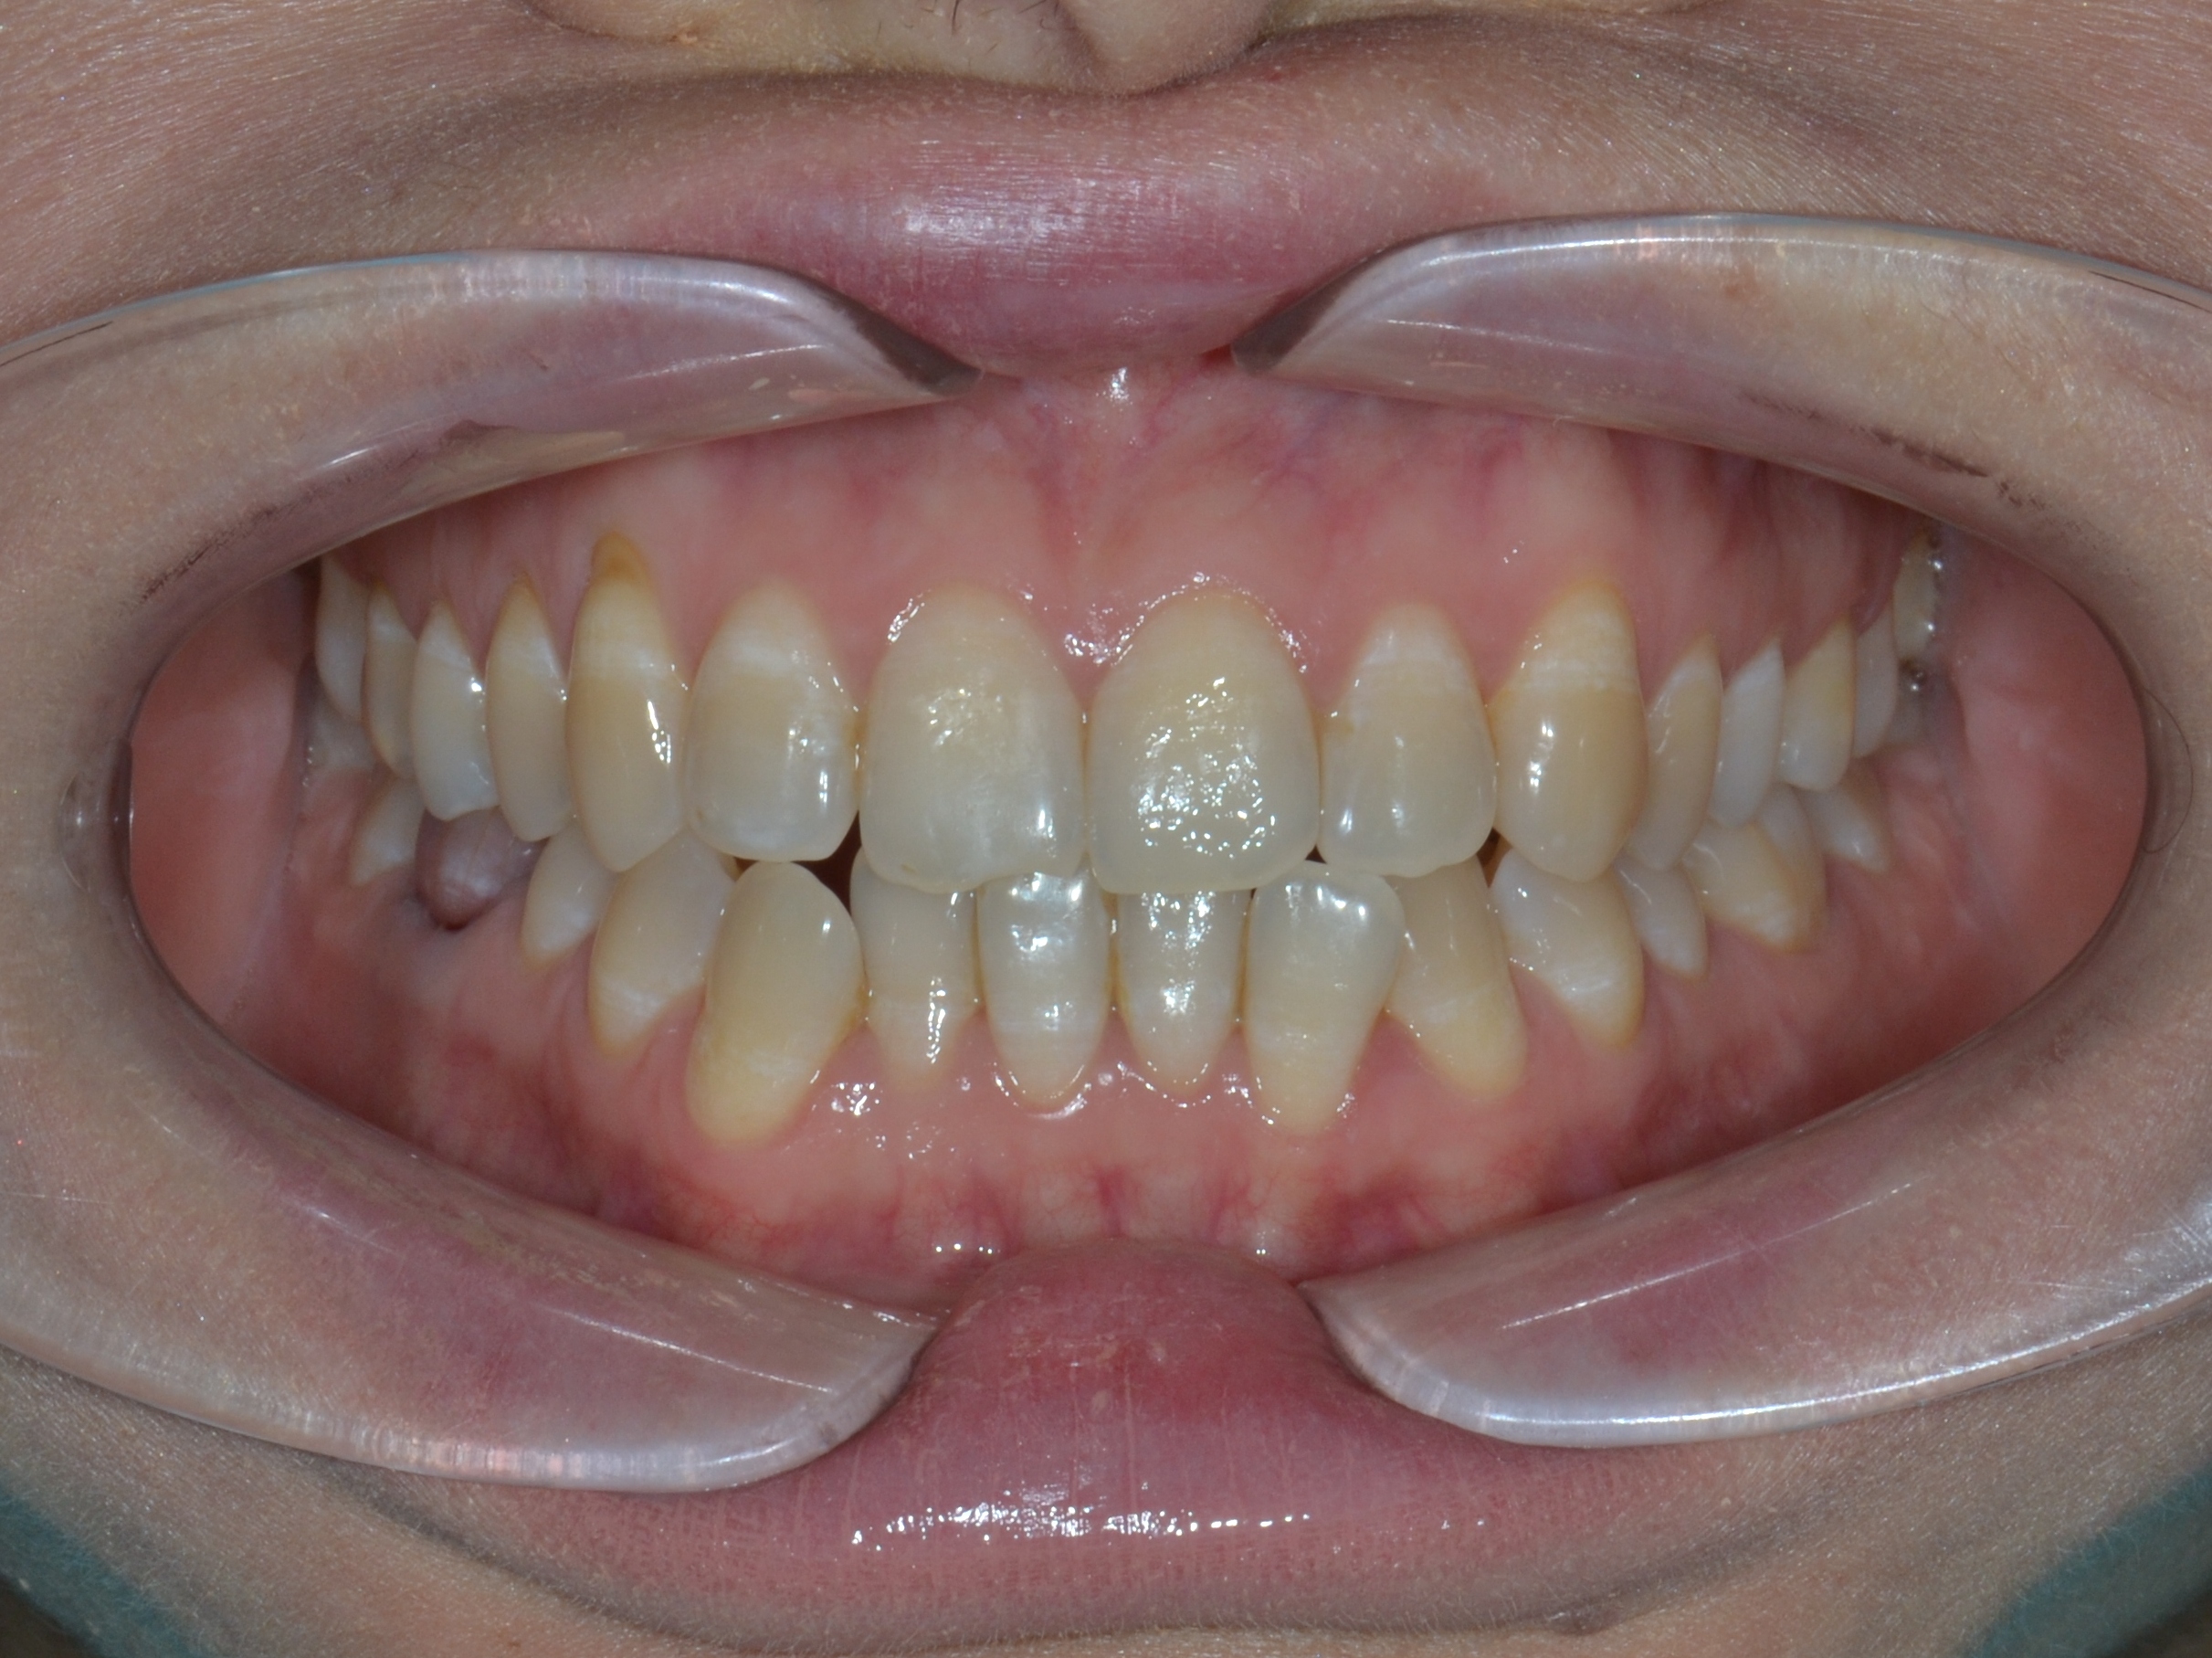

Выявленные проблемы

• Дистальная окклюзия ||(2)

• Глубокое резцовое соотношение

• Скученность фронтальных зубов

• Вестибулярное положение клыков

Брекет-система Ultra